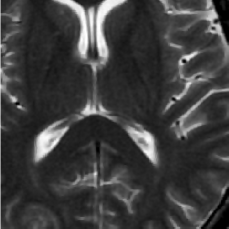

(d) Circle of Willis

Figure 2: Test Images.

We turn now to test TDIHT for high dimensional signals. We test the performance of several MRI images: the Shepp-Logan phantom, FLAIT brain image, T2 Sagittal view of the lumbar spine and the circle of Willis. The first image is of size 256×256256256256\times 256, while the other are of size 512×512512512512\times 512. They are all presented in Fig. 2.